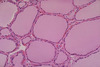

What tissue is this?

Thyroid